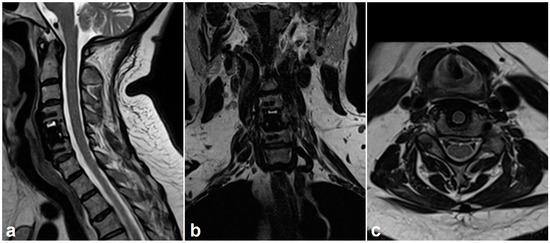

2.3. Radiologic Outcome

- Krätzig, T.; Mende, K.C.; Mohme, M.; Kniep, H.; Dreimann, M.; Stangenberg, M.; Westphal, M.; Gauer, T.; Eicker, S.O. Carbon fiber–reinforced PEEK versus titanium implants: An in vitro comparison of susceptibility artifacts in CT and MR imaging. Neurosurg. Rev. 2021, 44, 2163–2170. [Google Scholar] [CrossRef] [PubMed]